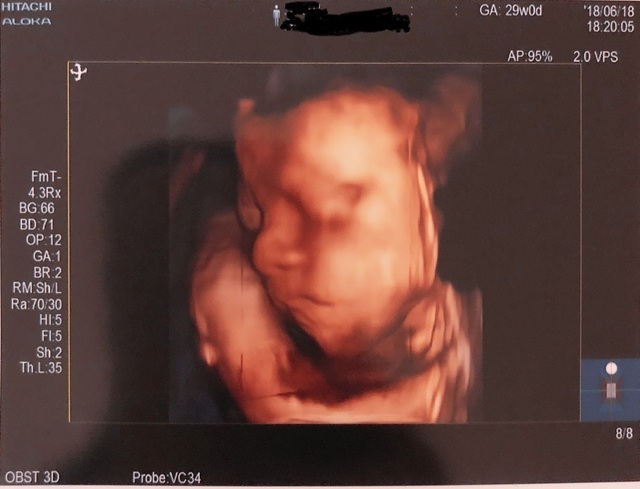

29週0日(29w0d・男の子)|haorinさん(29歳)

エコー写真撮影時のエピソード:

妊娠を通して悪阻は全くなく、とても楽しいマタニティライフでした。エコー写真でこんなにはっきり顔が見えて、愛おしさがさらに増しました。この時期はまだ産休にも入っていなかったので、周りの人に支えられながら働いていました。出産後、見比べても面影があります。